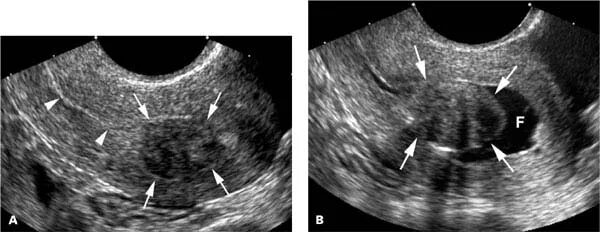

Диффузные изменения матки